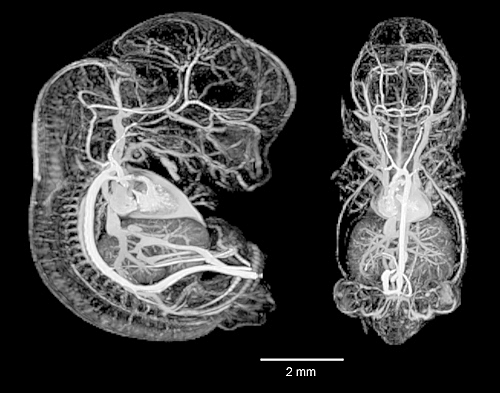

12.5-Day Mouse Embryo Vasculature

MRI with contrast material in blood vessels and heart to accentuate vascular details.

12.5 Day Mouse Embryo Vasculature